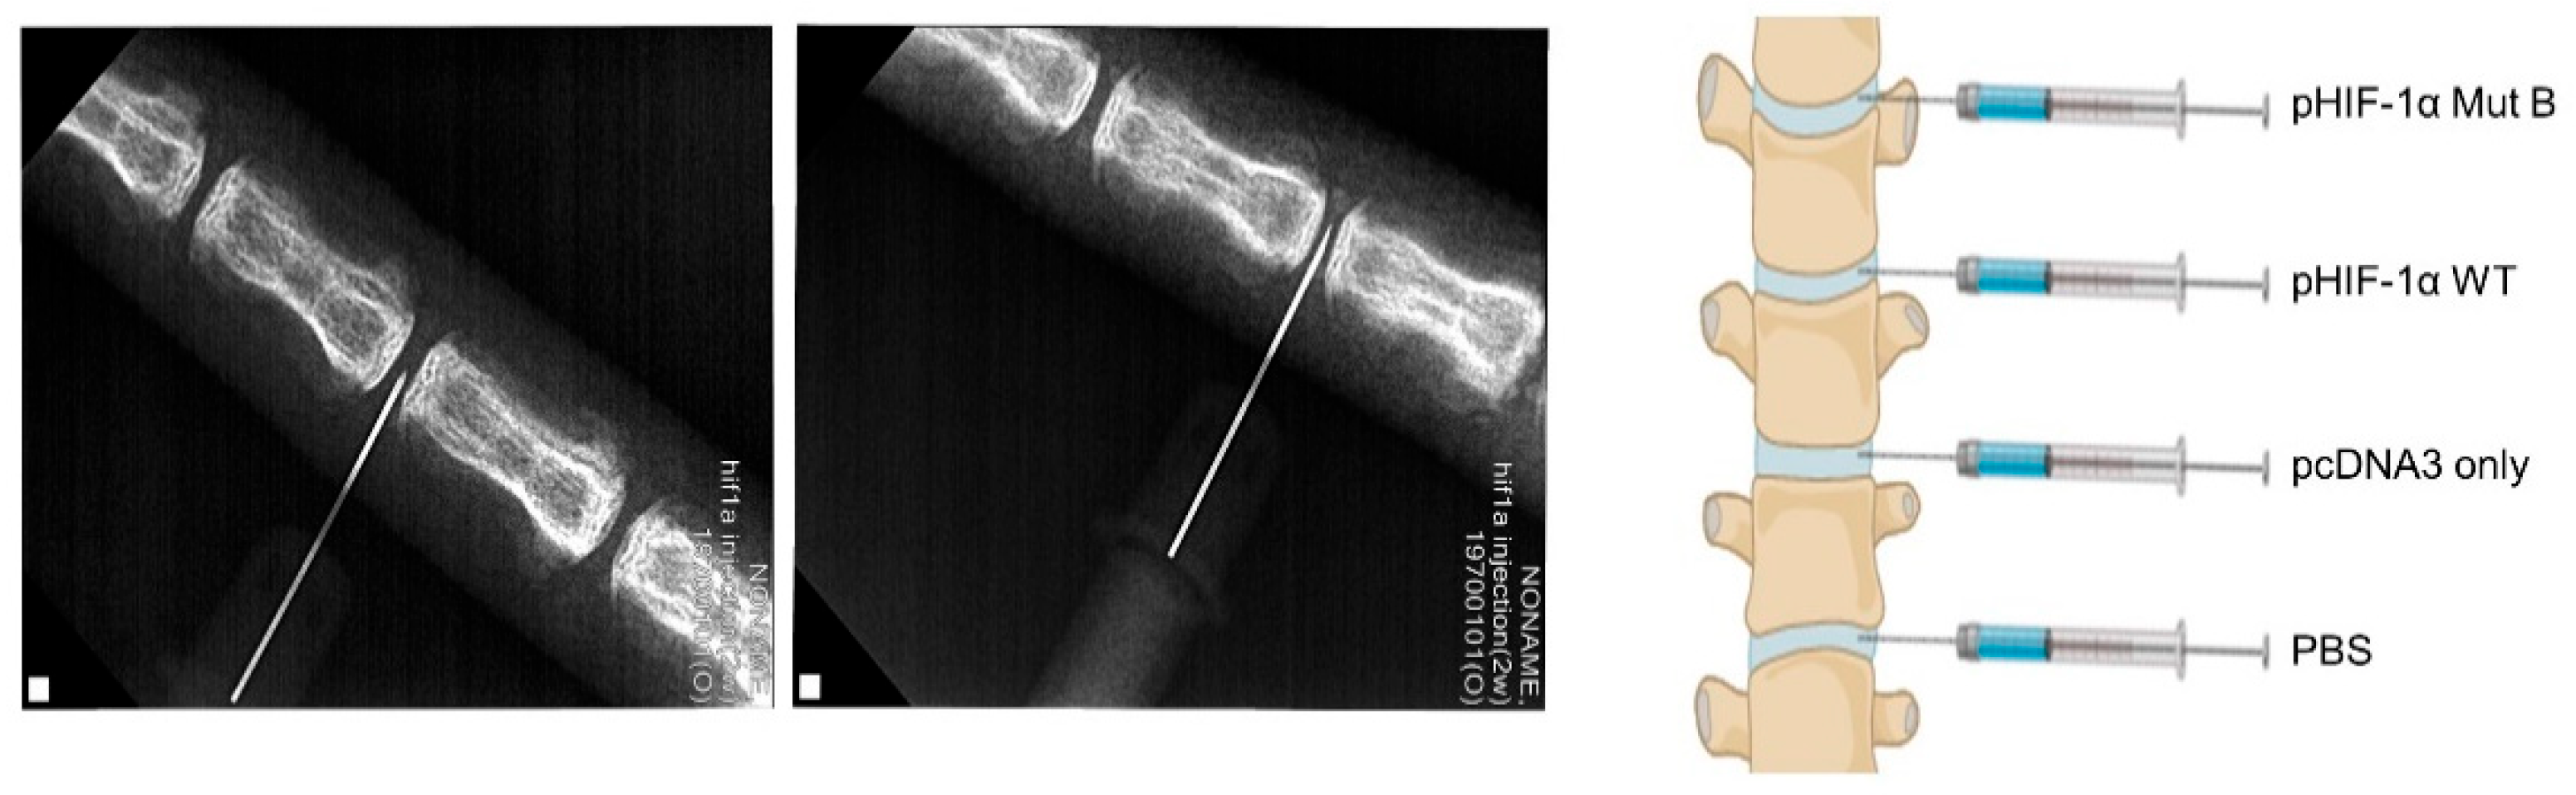

2.4. Radiographic and MRI Assessment, and Histological Evaluation of CA HIF-1α

4.11. Surgical Procedure

4.12. Radiographic and MRI Evaluation

4.13. Histological Analysis